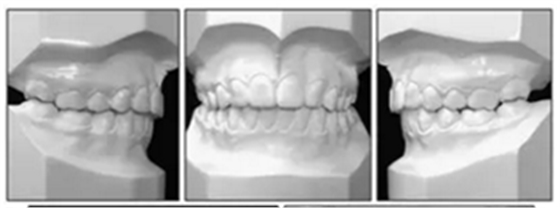

文獻(xiàn)優(yōu)秀正畸病例賞析--上頜側(cè)切牙缺損的病例介紹

患者是一名12歲5個月的女孩,主訴是上頜牙列擁擠和前牙開合(圖1)。同時講話也受到了影響。無顳下頜關(guān)節(jié)癥狀。曾有過上頜擴(kuò)弓和前牙排齊的正畸治療史。

口內(nèi)分析顯示呈II類1分類錯合畸形,前牙開合2mm和覆蓋3mm(圖2)。左側(cè)的后牙存在反合。上牙弓擁擠度2.5mm,下牙弓擁擠度1mm。中線一致。下頜前牙區(qū)牙齦稍有退縮。